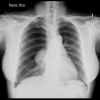

Bir çocukta pnömotoraks nasıl teşhis edilir?

Çocuğun hastalığının hikayesi ve fizik muayene bulguları teşhis için ilk adımdır.

Radyolojik olarak PA Akciğer grafisi ve Bilgisayarlı Tomografi ilk başvurulacak tetkiktir. USG deneyimli ellerde pnömotoraks tanısında yardımcı olur. BT yenidoğanda ve bebeklerde konjenital dediğimiz doğumsal akciğer anomalilerini ayırt etmede bizlere yardımcı olmaktadır. Çünkü konjenital akciğer anormallikleri pnömotoraksa benzer görüntü ile karıştırılabilir deneyimli radyoloji ve göğüs cerrahisi ekibine ihtiyaç duyulabilir.